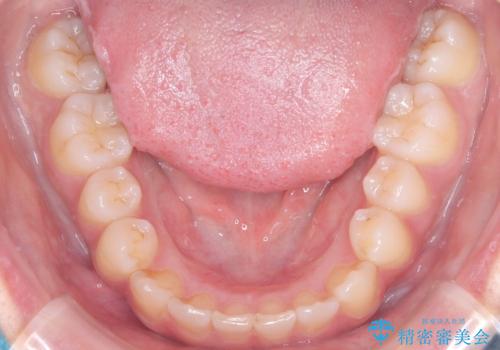

反対咬合と前歯のガタガタを非抜歯で改善

- 患者様は、上下の前歯のガタガタと反対咬合(下の歯が上の歯より前に出ている状態)を主訴として来院されました。診断の結果、抜歯を行わずに治療を進めるため、臼歯を遠心移動させてスペースを作り、IPR(インタープロキシマルリダクション)で歯間を調整する治療計画を立てました。インビザラインを使用して、透明で目立たない矯正装置により、歯列を整えながら噛み合わせも改善することを目標としました。

非抜歯での治療では、限られたスペースの中で効率的に歯を動かす必要があります。本症例では、臼歯を後方に移動させる遠心移動を行い、歯列のガタガタを改善しました。また、IPRを適切に行うことでスペースを確保し、歯根や歯肉への負担を最小限に抑えながら治療を進めました。インビザラインを使用することで、治療中も目立ちにくく、患者様の日常生活への影響を軽減しました。結果として、抜歯を行わずに美しい歯並びと自然な噛み合わせを実現し、患者様には大変満足していただけました。